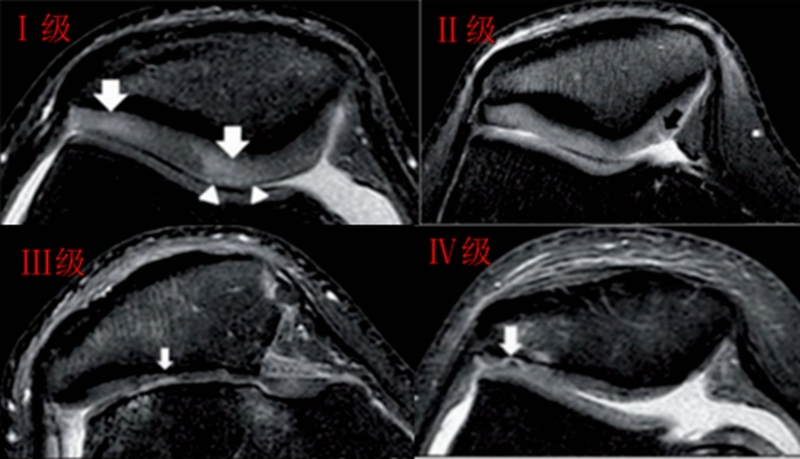

关节镜下可将髌骨软化分为5级

Ⅰ级:关节软骨失去珍珠样外观而变得较暗淡,局部软化,肿胀区或纤毛化区的直径<0.5cm。

Ⅱ级:关节软骨软化区内出现毛刷状或纤毛化改变,深达1-2mm,直径≤1.3cm。

Ⅲ级:软骨的毛刷状或纤毛化改变达关节软骨厚度一半以上,直径>1.3cm,关节软骨表面类似蟹肉样改变,表面有多发软骨碎片附着其下的软骨。

Ⅳ级:关节软骨全层受侵,软骨下骨暴露,表现为进展期髌股关节炎。

Ⅰ~Ⅱ级为早期,主要保守治疗,Ⅲ~Ⅳ级为进展期,需要手术及关节镜治疗。

髌骨软骨软化分级表现